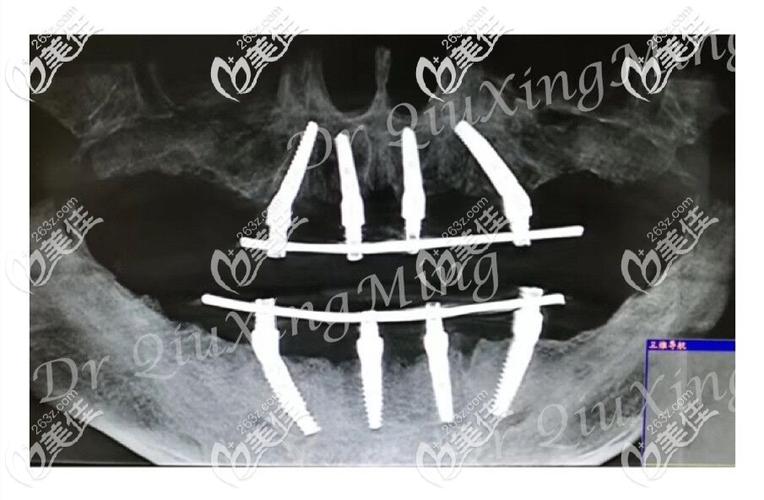

植牙图中,4颗种植体的分布是技术核心:前牙区(侧切牙位置)植入2颗种植体,通常垂直于牙槽骨,提供初期稳定性;后牙区(磨牙位置)植入2颗种植体,以30°-45°角度倾斜植入,这种设计有两个关键作用:一是避开上颌窦(上颌后牙区)或下牙槽神经管(下颌后牙区)等重要解剖结构,避免植骨手术;二是利用倾斜角度增加种植体与骨组织的接触面积,并通过力学分散咬合力,减少种植体承受的杠杆力,提升长期稳定性。

术前评估与设计:通过CBCT(锥形束CT)获取牙槽骨三维数据,在植牙图中标注关键解剖结构(如上颌窦底、下牙槽神经管),模拟种植体植入位置、角度及深度,确保避开危险区域,同时结合口腔模型,设计牙冠的形态、排列及咬合关系。

种植体植入:术中在牙槽骨上制备种植窝洞,按照植牙图设计的角度植入4颗种植体(常用直径4.0-5.0mm、长度10-13mm的钛种植体),前牙区垂直植入,后牙区倾斜植入,确保种植体尖端位于致密骨层以获得初期稳定性。